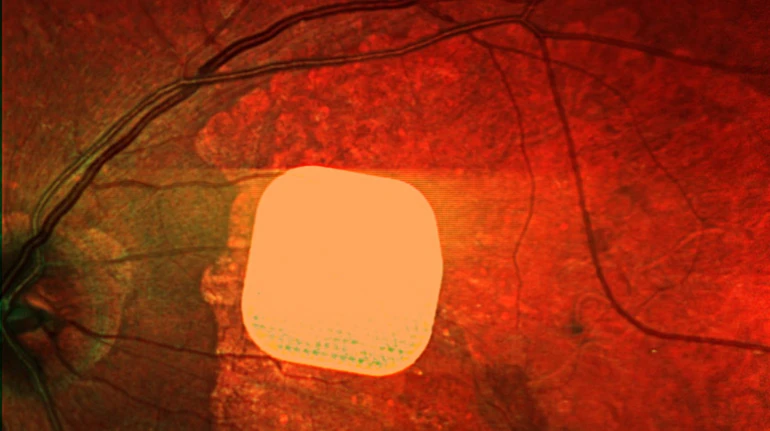

Імплант Prima – це мікрочип розміром 2×2 міліметри, який хірургічно розміщують під сітківкою ока. Під час операції, що триває менш як дві години, пацієнту встановлюють пристрій, який потім працює разом з окулярами доповненої реальності.

Новий електронний очний імплант за розміром як SIM-карта

Фото: Science Corporation/PA